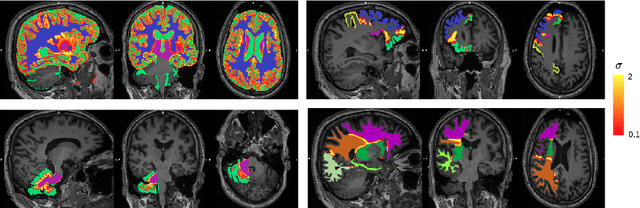

Abstract:Combining multi-site data can strengthen and uncover trends, but is a task that is marred by the influence of site-specific covariates that can bias the data and therefore any downstream analyses. Post-hoc multi-site correction methods exist but have strong assumptions that often do not hold in real-world scenarios. Algorithms should be designed in a way that can account for site-specific effects, such as those that arise from sequence parameter choices, and in instances where generalisation fails, should be able to identify such a failure by means of explicit uncertainty modelling. This body of work showcases such an algorithm, that can become robust to the physics of acquisition in the context of segmentation tasks, while simultaneously modelling uncertainty. We demonstrate that our method not only generalises to complete holdout datasets, preserving segmentation quality, but does so while also accounting for site-specific sequence choices, which also allows it to perform as a harmonisation tool.

Abstract:Being able to adequately process and combine data arising from different sites is crucial in neuroimaging, but is difficult, owing to site, sequence and acquisition-parameter dependent biases. It is important therefore to design algorithms that are not only robust to images of differing contrasts, but also be able to generalise well to unseen ones, with a quantifiable measure of uncertainty. In this paper we demonstrate the efficacy of a physics-informed, uncertainty-aware, segmentation network that employs augmentation-time MR simulations and homogeneous batch feature stratification to achieve acquisition invariance. We show that the proposed approach also accurately extrapolates to out-of-distribution sequence samples, providing well calibrated volumetric bounds on these. We demonstrate a significant improvement in terms of coefficients of variation, backed by uncertainty based volumetric validation.

Abstract:Many atlases used for brain parcellation are hierarchically organised, progressively dividing the brain into smaller sub-regions. However, state-of-the-art parcellation methods tend to ignore this structure and treat labels as if they are `flat'. We introduce a hierarchically-aware brain parcellation method that works by predicting the decisions at each branch in the label tree. We further show how this method can be used to model uncertainty separately for every branch in this label tree. Our method exceeds the performance of flat uncertainty methods, whilst also providing decomposed uncertainty estimates that enable us to obtain self-consistent parcellations and uncertainty maps at any level of the label hierarchy. We demonstrate a simple way these decision-specific uncertainty maps may be used to provided uncertainty-thresholded tissue maps at any level of the label tree.